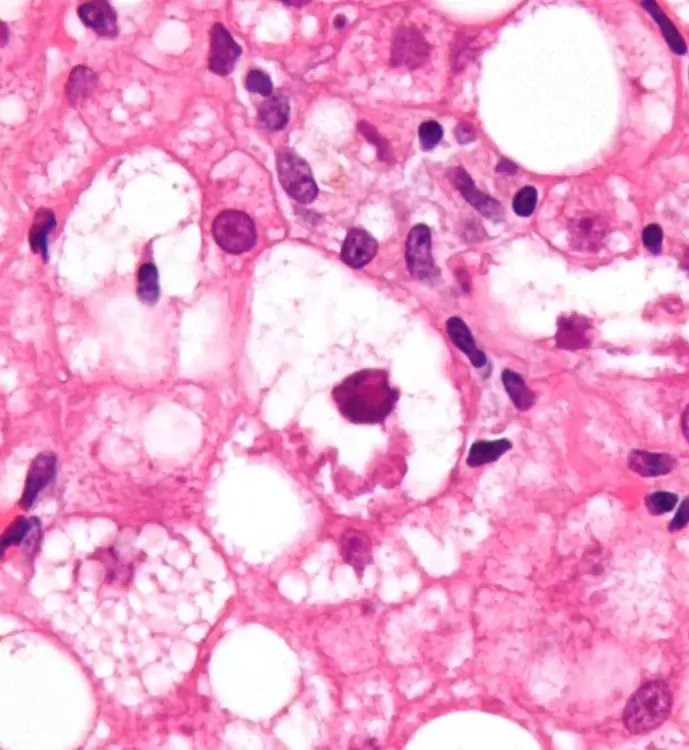

The disease was initially formally known as Primary Biliary Cirrhois (PBC). It has now been changed to Primary Biliary Cholangitis, because it involves a variety of physiological effects—more than just cirrhosis of the liver. Among the general population PBC is rarely found. But as it affects First Nations at a rate of two in every 2,000, the disease develops eight times higher than with non-First Nations people. PBC is even more common in aboriginal communities on the West Coast of B.C., where 48 per cent of Canada’s First Nations people with the disease are located. There is no known cure at this time, though there are treatments for it, and preventative measures, as well.

Nonetheless, the disease isn’t pretty, or fun, once it’s developed. And it causes a variety of other problems, too.

“The bile duct kind of disappears and it also causes jaundice. In the First Nations population there seems to be more autoimmune liver disease like this, and like autoimmune hepatitis, the cousin of PBC,” he said.